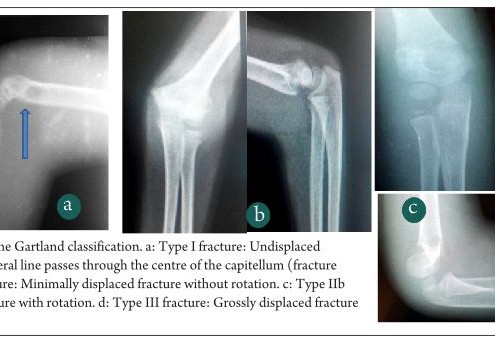

Classifications of Supracondylar Humerus Fractures: Are they Relevant? Are we Missing Something?

Vol 1 | Issue 1 | July-Sep 2015 | page:6-10 | Mandar Agashe.